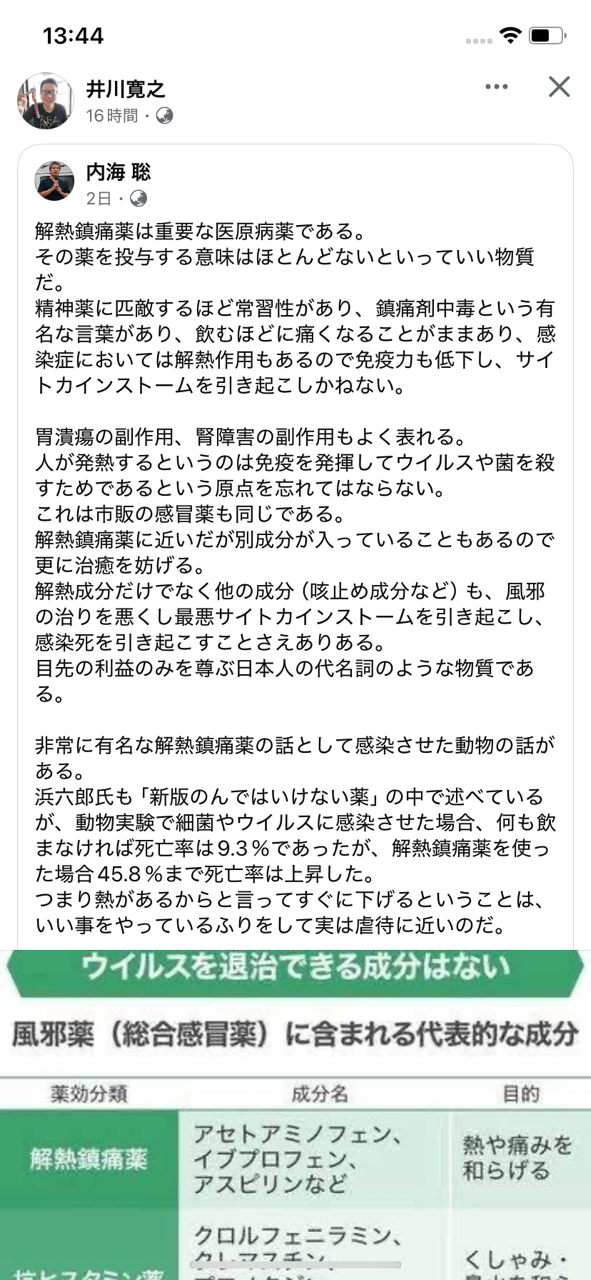

有名な薬でも医者の言いなりに飲むのはこんなに危険です! 出典・フェイスブック

解熱鎮痛薬は医療病薬 出典・フェイスブック